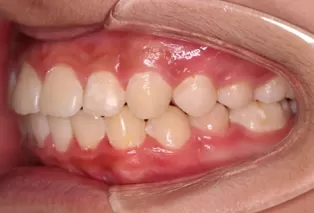

Intraoral photos after treatment